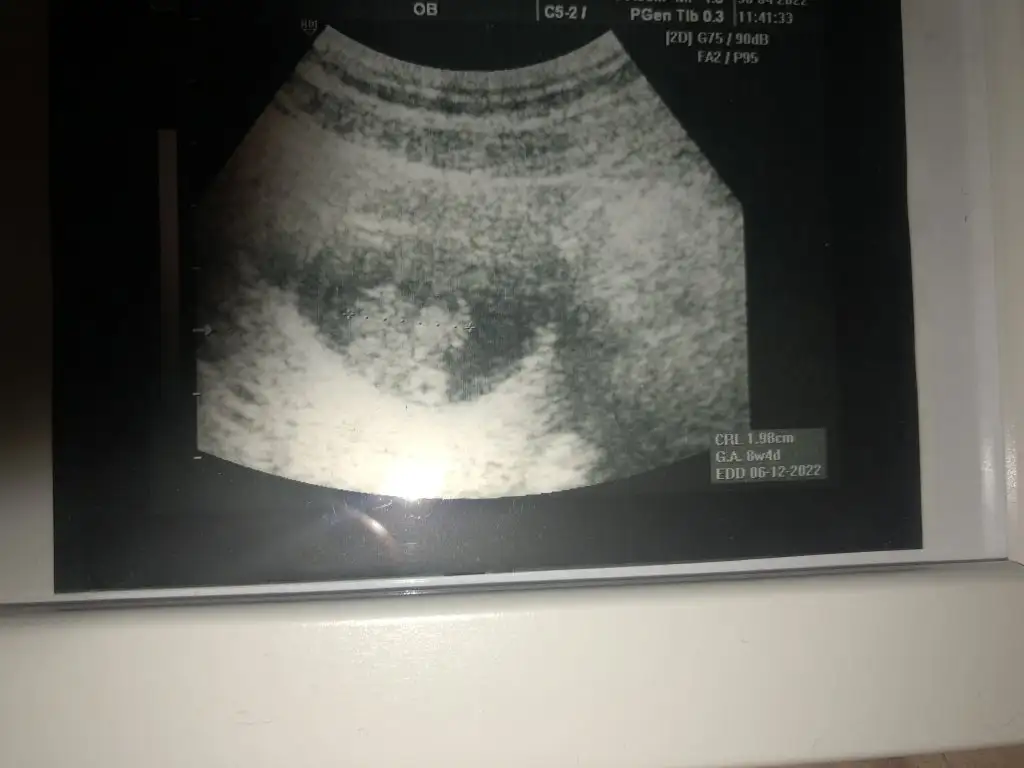

5 ve 14. haftaya kadar olan ultrason fotolarınızı paylaşın. Vajinadan mı yoksa karından mı çekildiğini ve kaç haftalık olduğunu da mutlaka belirtin.

simsiyah bir görüntü canım maalesef belli olmuyor10 hafta karindan tahmin edermisin canim